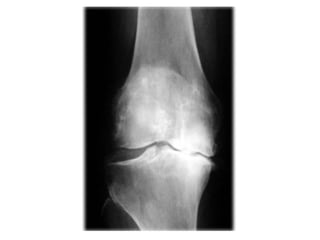

Artrosis Velvetización Fisuración Ulceración Eburnización

Artrosis Velvetización FisuraciónUlceración Eburnización